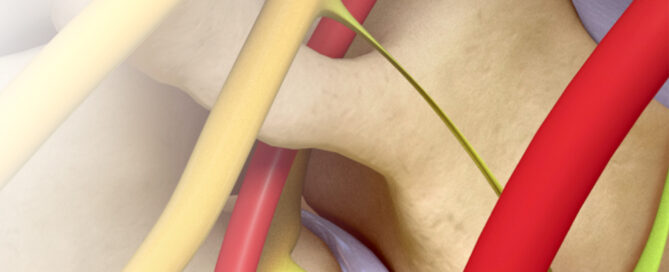

Discover why so many clinicians use the blunt needle for atraumatic access to nerve blocks, sleeve blocks, deep muscle blocks, hypogastric, paravertebral blocks, joint blocks, facets, selective nerve root, lumbar sympathetic, thoracic sympathetic, splanchnic, and celiac plexus blocks.